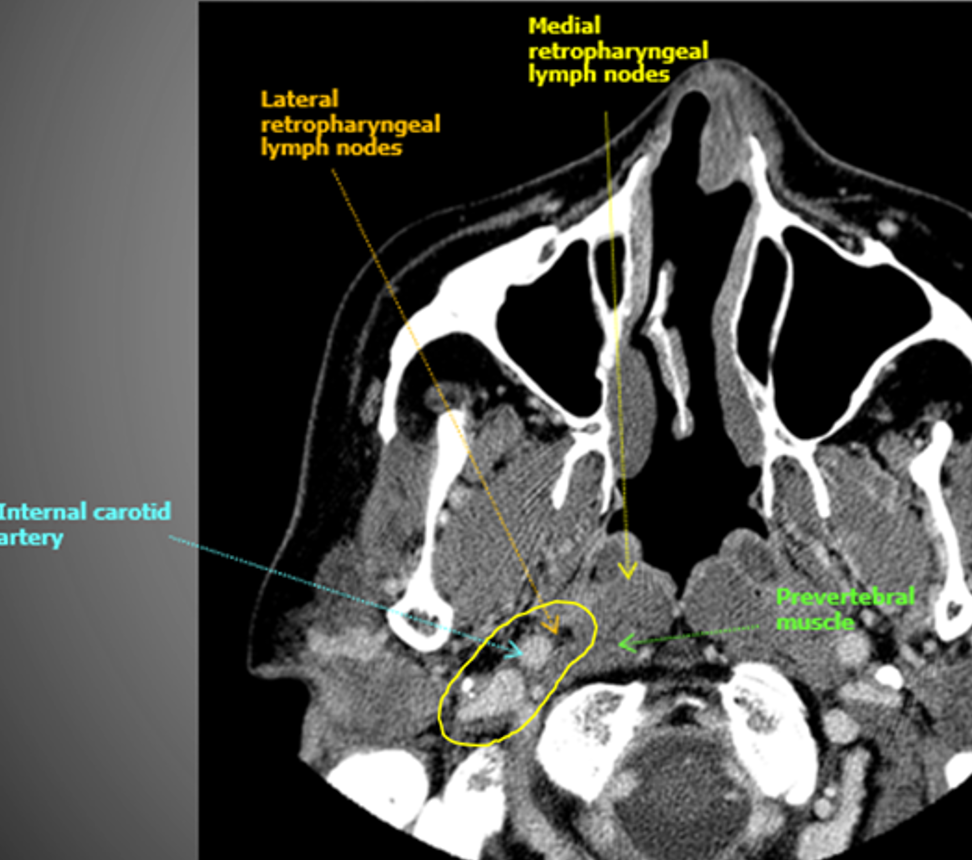

How I do it: defining retropharyngeal nodes at risk

Remember that there are lateral and medial retropharyngeal lymph nodes (RPLNs). When there is pathologic involvement of RPLNs, it is almost always the lateral RPLN that is involved first. Note that the lateral RPLN space is the fat space (dark on CT) immediately medial to the internal carotid artery.

When electively treating the retrostyloid and RPLN as in this case, I usually only treat the lateral RPLN. If the RPLN was grossly involved with cancer, I would include both the lateral and medial RPLNs.